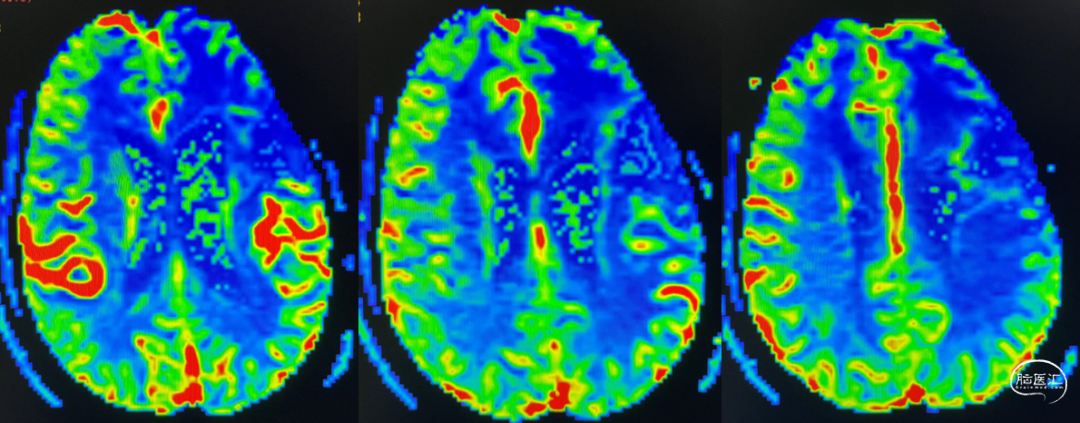

放疗后17月(2021-12-20)PWI显示感兴趣区脑血容量及血流量较对侧高低不一,平均通过时间及达峰时间延长,提示左侧病变区血流灌注降低:图示。

辅助TMZ治疗过程中每2-3月复查MRI。治疗中曾出现水肿范围增大,尽管有部分区域弥散受限和MRS异常及血流量增加,但是临床症状未加重,仍继续原方案治疗,后续监测PWI显示病变区灌注减低。提示持续肿瘤电场治疗可以使病变长期稳定。此患者每天佩戴肿瘤电场治疗时间接近22小时,中间出现头皮发红和小水泡,经局部外用皮质类固醇和外用抗生素,暂停2天治疗恢复。至今随访25月稳定。说明肿瘤电场治疗联合TMZ治疗较单TMZ治疗明显延长胶质母细胞瘤患者PFS及OS,临床应积极推广使用。